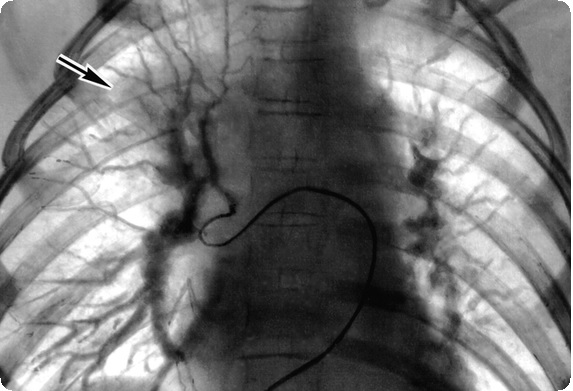

Ангиокардиографическое исследование обязательно должно включать правую атриографию, левую вентрикулографию, легочную артериографию в аксиальной проекции и аортографию. При правой атриографии контрастное вещество, минуя правый желудочек, поступает в левое предсердие и далее в левый желудочек. При этом в переднезадней проекции непосредственно над диафрагмой между контрастированными правым предсердием и левым желудочком всегда выявляется неконтрастируемый участок треугольной формы, который располагается в месте приточной части правого желудочка. Это так называемое окно правого желудочка, являющееся характерным признаком АТК.